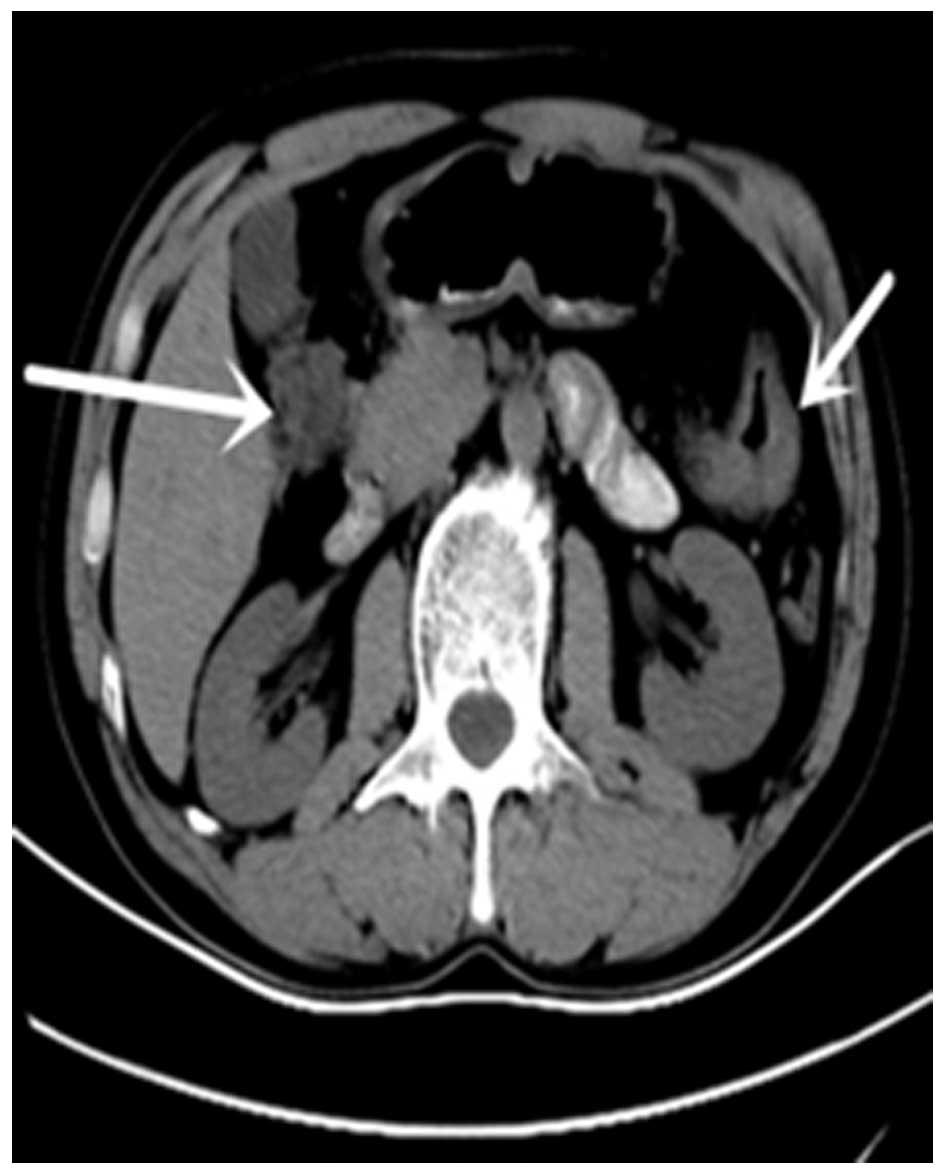

A C Ct Scan Abdomen And Pelvis With Contrast Of An 80 Yrs Old Male Download Scientific Diagram

www.researchgate.net